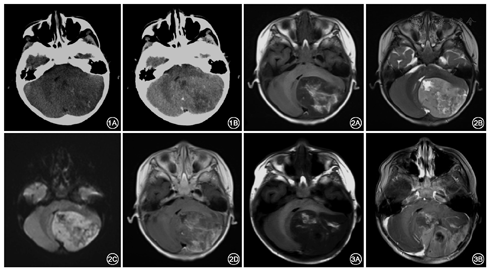

患儿男,2岁4个月,头向右侧歪斜伴呕吐半月余,步态不稳1周收住入院。查体:闭目难立征(+),指鼻实验不能配合,其余未见异常体征。CT示左侧小脑半球7.9 cm×4.7 cm×5.3 cm大小等密度肿块,内见片状低密度区及点条状高密度影,边界清,周围未见水肿,增强后强化不明显(图1);MRI示肿块呈长T1WI稍长T2WI信号,内见不规则斑片状短T1WI混杂T2信号,DWI扩散受限,ADC图等低信号;增强后呈不均匀斑片状轻中度强化,病灶紧贴硬膜及左侧小脑幕,近硬膜处强化相对明显(图2)。术前诊断:后颅窝占位伴出血,考虑:(1)非典型畸胎瘤样横纹肌样瘤(AT-RT);(2)髓母细胞瘤。手术切开后枕部硬脑膜,硬膜下见肿瘤组织色灰黑,质软,血供丰富,与小脑幕粘连,部分病变组织内为黄组织,血供少,予显微镜下全切肿瘤组织。病理结果示大体标本见灰白灰黄色组织,切面灰红色,实性,质软。镜下见低分化小到中等大小细胞,形成多层菊形团伴坏死。免疫组化:钙结合蛋白S100(-),胶原纤维酸性蛋白GFAP(-),波形蛋白Vim(+++),上皮膜抗原EMA(核旁点状+),P53(-),细胞增殖抗原Ki67(约50%+),突触素Syn(灶+),神经元特异核蛋白NenN(灶+),整合酶相互作用分子INI-1(+++)。病理诊断:高级神经源性肿瘤,WHO Ⅳ级,倾向胚胎性肿瘤伴多层菊形团,非特殊类型。术后出院5个月后原部位复发(图3)。

影像学上主要表现为较大的实性肿块,可伴有囊性成分,既往文献十余例报道肿瘤累及硬脑膜;尸检发现肿瘤实体与周围脑组织有明显的分界[4],并非向周围浸润生长,故瘤周无或轻度水肿。Gessi等[5]报道29例ETANTR,表现为无强化、不均匀强化、或片状不完全强化,1例为均匀强化;从强化程度来看,血脑屏障破坏不明显,其多种强化形式可能与其不同比例的各细胞成分区及重新建构的血管床有关。Wang等[6]报道了7例ETMR,均为实性,4例基本无强化、3例轻度强化,认为其强化方式与和正常脑组织相似的大量的神经毡成分有关。本例ETMR发生于相对不常见的小脑半球,为较大的实性肿块,累及硬脑膜及小脑幕,DWI明显高信号,ADC低信号为典型恶性肿瘤征象,但强化不充分,呈片状不完全强化即补丁样强化且周围未见水肿,因对该类肿瘤认识不足术前误诊为AT-RT、髓母细胞瘤。其发病部位、年龄且伴较多出血与AT-RT相似,但后者常可见较大偏心囊变,且瘤周水肿明显,多可见明显条状或环状强化,INI-1阴性;髓母细胞瘤多位于中线结构,强化明显且相对均匀,出血少见,但位置及强化不典型者鉴别较困难,此外尚需与神经母细胞瘤鉴别,后者除脑实质外、脑室、脊髓、硬膜下及颅外均可累及,易囊变出血坏死、可伴有钙化,累及范围广,增强后呈中度或明显强化,但与ETMR类似,瘤周水肿相对较轻。当年龄较小患儿脑实质内出现较大实性为主占位,且DWI高信号与周围轻水肿、强化不明显间"不匹配"时,要考虑到ETMR的可能。

ETMR预后较差,早期即可有转移,多在发病后1年内死亡,本例术后5个月即原部位复发,两次MRI检查均可见瘤内片状出血,反映肿瘤恶性程度高、生长旺盛。肿瘤全切、放疗及高剂量化疗可提高生存期[7],但总体疗效不佳。